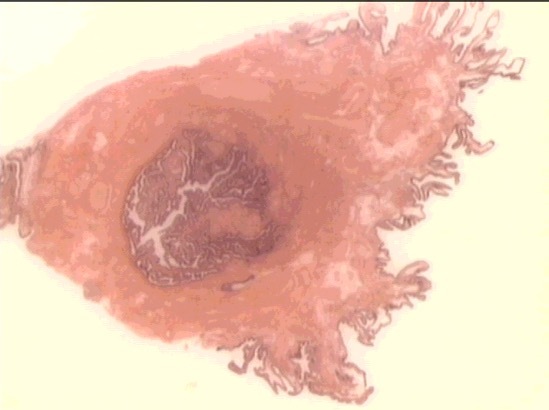

distal fallopian tube

infundibulum

fimbria

mid-oviduct

ampulla

isthmus near uterus